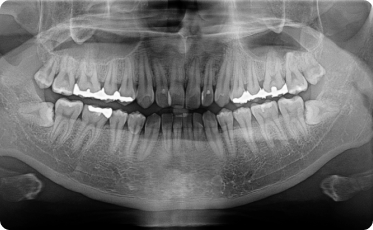

Технологии Ray обеспечивают самое лучшее качество и высокую чёткость панорамных снимков

Байт-Винг

Ортогональный

ВНЧС